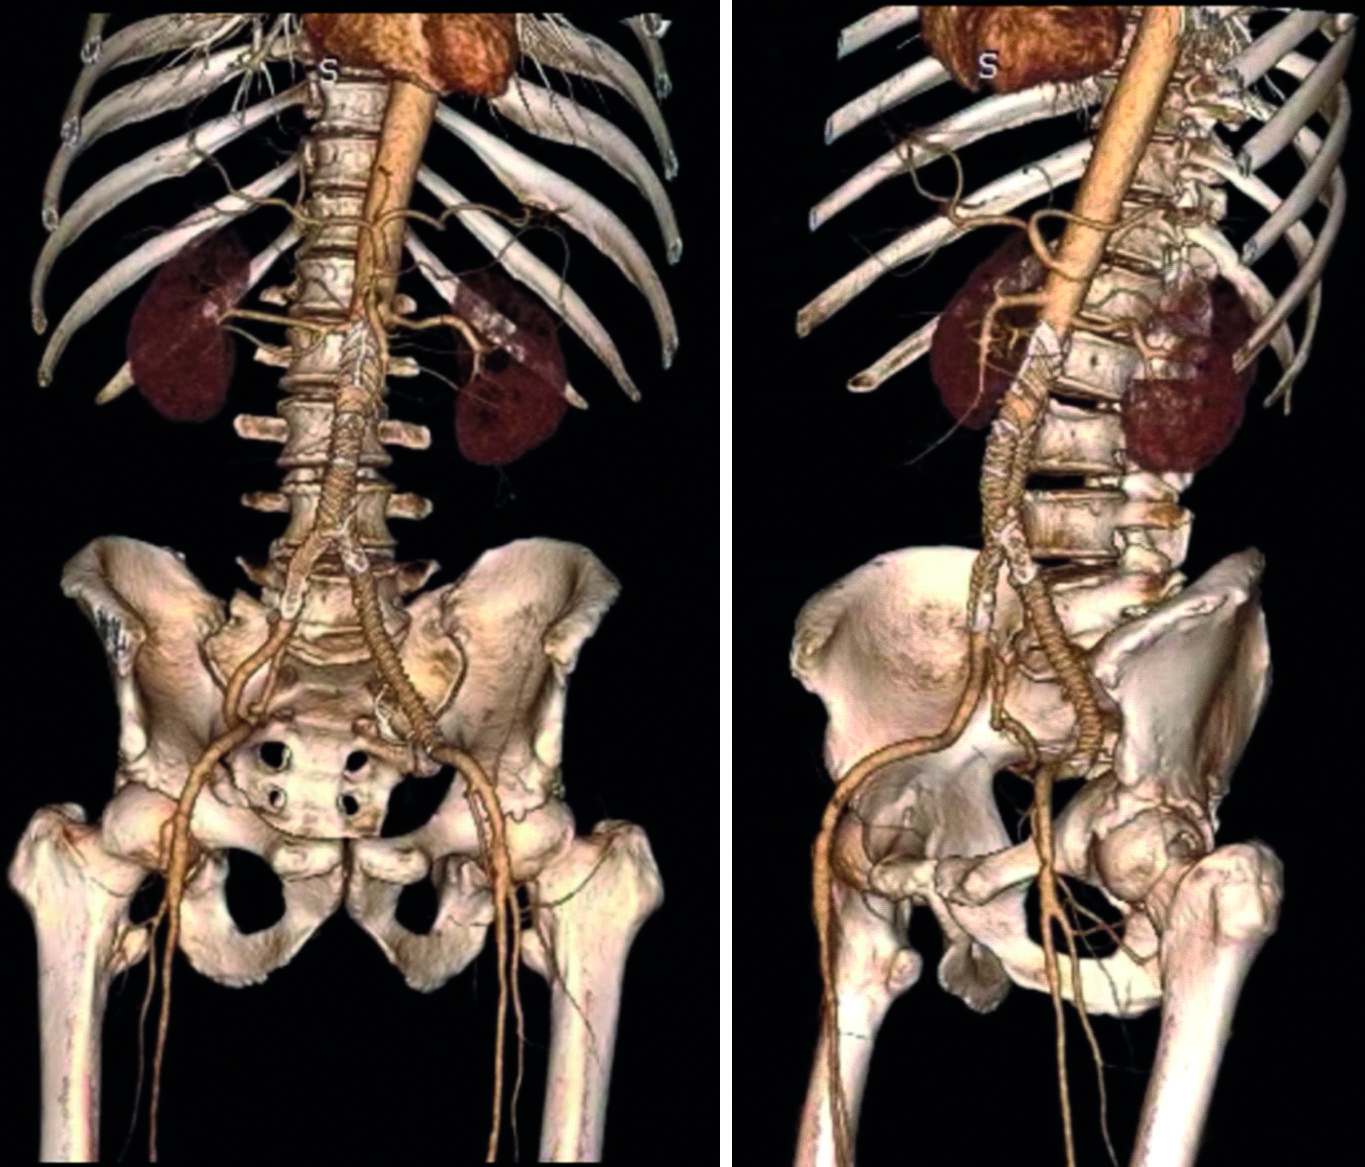

On December 19, 2020, endoprosthetics of the abdominal aorta and left common iliac artery was performed using the Aorfix endoprosthesis (Fig. 2).

Figure 3. 3D reconstruction after endoprosthetics.

Рисунок 3. 3D-реконструкция после эндопротезирования.

In the second stage, the patient was operated on at the N.N. Blokhin National Medical Research Center of Oncology. On February 2, 2021, the tumor was removed with nephrectomy and hemicolectomy on the left, resection of the infrarenal segment of the abdominal aorta and the left common iliac artery. Intraoperative revision: a massive tumor of dense consistency, up to 20×25×19 cm in diameter, is determined in the left retroperitoneum with spread to the left iliac region. The tumor grows into the mesentery of the descending colon; the left ureter passes a long distance in the mass of the tumor.

The previously installed endoprosthesis is positioned adequately, without signs of extravasation. The tumor infiltrates the infra-renal segment of the aorta and the left common iliac artery. The tumor was mobilized by excision. Left section of the large bowel was mobilized. The infra-renal section of the aorta was circumferentially mobilized, and the left and the right common iliac arteries held in the holder. The left branches of the middle colic vessels, the left colic vessels, and the inferior mesenteric vein were isolated, ligated, and transected. The transverse colon was cut in its middle third and the descending colon in its distal third with the linear cutter stapler. The left kidney was mobilized, the left renal vessels and left ureter were isolated, ligated and transected. Aortic wall resection of 3×4 cm was performed. The tumor was removed in a single block without damage to the integrity of its pseudocapsule together with the left kidney, left half of the large intestine and the wall of the infra-renal segment of the abdominal aorta 6 cm long and of the left common iliac artery (Fig. 4). The integrity of the large bowel was restored by means of two-layer transversosigmoid anastomosis. The duration of the operation was 210 minutes; the total blood loss was 350 ml.

Figure 4. View after tumor removal. Blue arrow – Aorfix endoprosthesis of the infrarenal segment of the abdominal aorta, yellow – Aorfix endoprosthesis of the left common iliac artery.

Рисунок 4. Вид после удаления опухоли. Синяя стрелка – эндопротез Aorfix инфраренального сегмента брюшной аорты, желтая – эндопротез Aorfix левой общей подвздошной артерии.